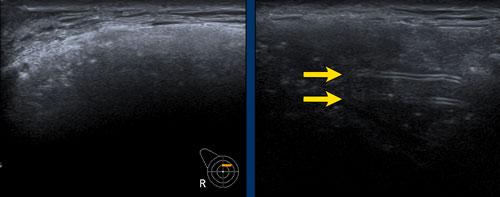

Dấu hiệu Oreo ngược

Vỏ bọc của túi độn có thể được nhìn thấy như một chiếc bánh Oreo lật ngược. Đường trắng đầu tiên là mặt tiếp xúc bên ngoài của vỏ bọc và đường trắng thứ hai là mặt tiếp xúc bên trong giữa vỏ bọc và gel Silicone (mũi tên vàng).

Giữa lớp ngoài của vỏ bọc và bao xơ xung quanh tồn tại một khoang ảo có thể được lấp đầy và giãn rộng.

Bao xơ được nhìn thấy tách biệt khỏi vỏ bọc như một đường trắng riêng biệt nằm phía trước vỏ bọc (mũi tên trắng).

Vỏ bọc và bao xơ cùng nhau được gọi là phức hợp vỏ bọc-bao xơ.

B. Vỏ bọc bị xẹp (mũi tên vàng) và không đi theo phức hợp vỏ bọc-bao xơ bên ngoài (mũi tên trắng).